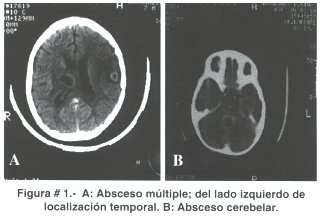

La diseminación directa sucede en 20 a 60% de casos y usualmente da lugar a un absceso simple; cuando el origen es otomastoideo el asiento de la infección generalmente es el lóbulo temporal y el cerebelo (figuras # 1 A y B), en tanto que los frontales y parietales (figura # 2) son afectados cuando la infección parte de los senos paranasales (maxilares, etmoidales, frontales) o abscesos dentarios(5).

Estudios experimentales sostienen que el absceso se forma en áreas de cerebro dañadas por efecto de hipoxia, hemorragia, infarto, necrosis o trauma directo, posteriormente se instala una cerebritis séptica con respuesta inflamatoria difusa en la que participan leucocitos polimorfonucleares. Días o semanas después existe necrosis y licuefacción en el centro de la lesión, a tiempo que se va configurando la cápsula (perilesional) compuesta por fibroblastos, macrófagos y astroglia; ésta puede ser de algunos milímetros o alcanzar varios centímetros, especialmente en los abscesos crónicos y en todos los casos siempre se encuentra edema circundante(9) como se observa en las figuras # 2 y 3. En términos generales se acepta que el tiempo que media en constituirse la cápsula es de 10 a 13 días.

Tanto la resonancia magnética como la tomografía computarizada son pruebas que definen el diagnóstico de absceso cerebral; con ambas se puede establecer claramente el área de cerebritis, la cápsula y el edema perilesional (figura # 2), sin embargo a IRM se le otorga mayor utilidad al momento de precisar el diagnóstico frente a masas tumorales o abscesos con tendencia a romperse en el sistema ventricular(10,13), asimismo cabe destacar que es un método más sensible en la detección de cerebritis temprana, para observar lesiones satélite, visualizar mejor el tallo cerebral y es más segura para estimar la extensión de la necrosis central. La resolución de la TAC es suficiente para definir el diagnóstico de AC; en etapas tempranas el parénquima cerebral comprometido se caracteriza por cambios de baja densidad mal definidos, para posteriormente, al momento de administrar medio de contraste, observar el clásico anillo bien definido de la cápsula rodeada de edema. En la mayoría de casos el absceso es único, sobre todo cuando el origen es una infección de senos paranasales y otomastoides, en cambio cuando la siembra es hematógena existe mayor tendencia a la formación de abscesos múltiples e incluso multilobulados(14) (figura # 4 A y B).